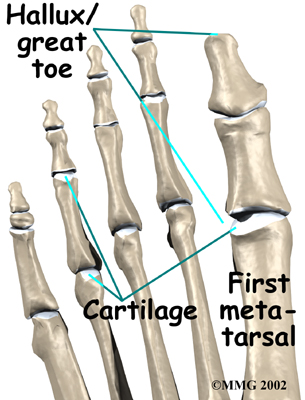

The big toe in medical terms is called the hallux. The joint at the base of the big toe is called the metatarsophalangeal, or MTP, joint. Like any other joint in the body, the joint is covered with articular cartilage, which is a slick, shiny covering on the end of the bone. If this cartilage is injured, it begins a slow process of wearing out, or degeneration. The articular surface can wear away so much that eventually raw bone rubs against raw bone.

Bone spurs form around the joint as part of the degenerative process. The spurs, or bony outgrowths, may restrict the motion in the joint, especially the ability for the toe to bend upward as the body moves forward over the foot, such as when you are taking steps. The big toe becomes very stiff or immobile into this range of motion, hence the reference to rigidity in the name of this condition.